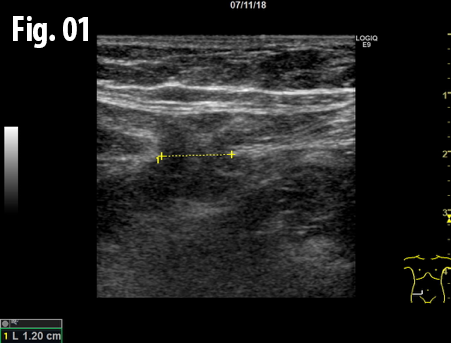

An ultrasound examination of the abdomen was performed using a GE Logiq E9 system with a linear array transducer and centre frequency of 9 MHz. The patient was examined in the supine and standing position including the Valsalva manoeuvre. The examination revealed an incarcerated hernia between the rectus abdominis and transversus abdominis muscles at the level of the anterior superior iliac spine. The dimension of hernial orifice was 1.3 x 0.7 cm and contained preperitoneal fat without any bowel loops. There was no change in size or content of the hernia on standing or Valsalva, and no signs of strangulation.

Figure 2: The hernia containing preperitoneal fat, sagittal view, patient standing. The marker indicates the hernia.